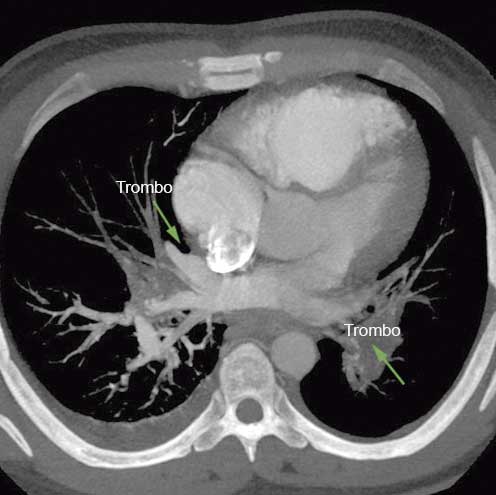

La angiotomografía pulmonar inicial (figura 4), mostró la presencia de trombos tanto en la arteria pulmonar izquierda, como en los ramos superior e inferior de la arteria pulmonar derecha, derrame pleural derecho y un nódulo pulmonar subpleural izquierdo en segmento posterobasal.

Angiotomografía cardiaca previa a la terapia fibrinolítica. Imagen de trombos organizados en la rama derecha e izquierda de la circulación pulmonar